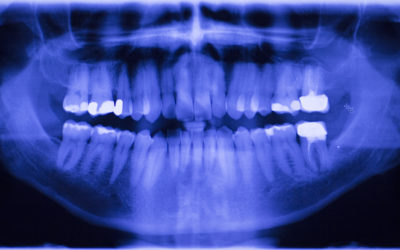

Dental X-Rays – What’s the Purpose?

Radiography is the use of x-rays in dental practice to create images of the teeth, bones, and surrounding tissues. Radiographs help dentists identify cavities, bone loss, infections, tumors, and other abnormalities that may not be visible during a clinical...